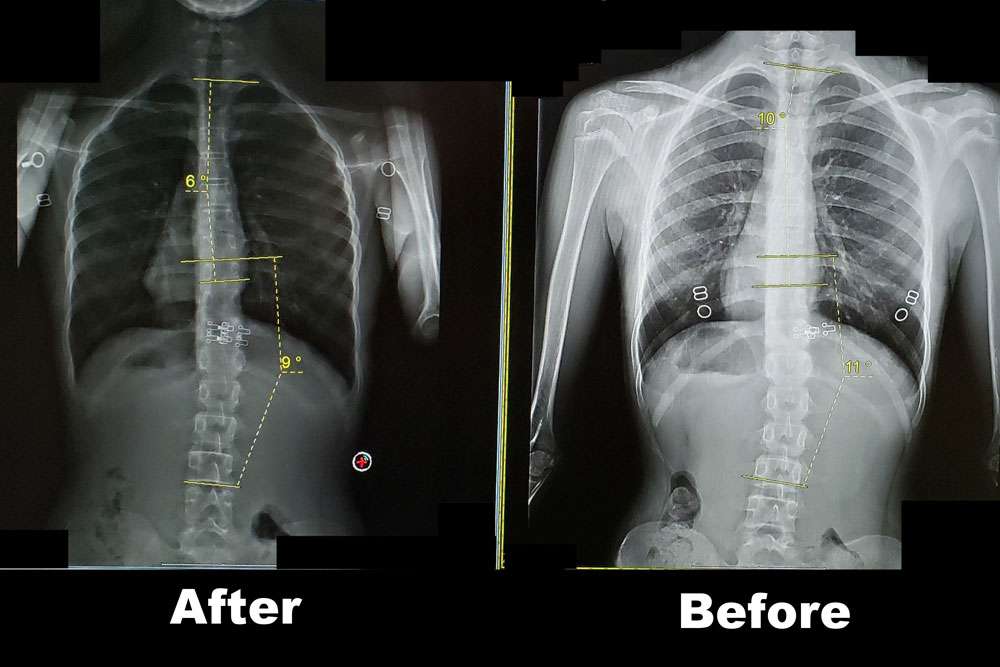

Scoliosis is measured on x-ray as a Cobb Angle. This measurement tells us how bad the scoliosis is and then guides us in how we treat it. Curves under 10 degrees usually aren’t considered scoliosis. Those curves 10-25 are called mild curves and we treat them with scoliosis specific exercise. Curves 25-45 degrees are treated with scoliosis specific exercise and bracing. Those above 45 degrees are usually surgical candidates. There is a measurement error of 3-5 degrees, which means to really have significant change, it needs to be above that.

Here are some examples of what can be done with scoliosis specific exercise with a variety of patients. The main goal of treatment is to STOP progression of the curve. With hard work and dedication we can also see reduction in the curve.